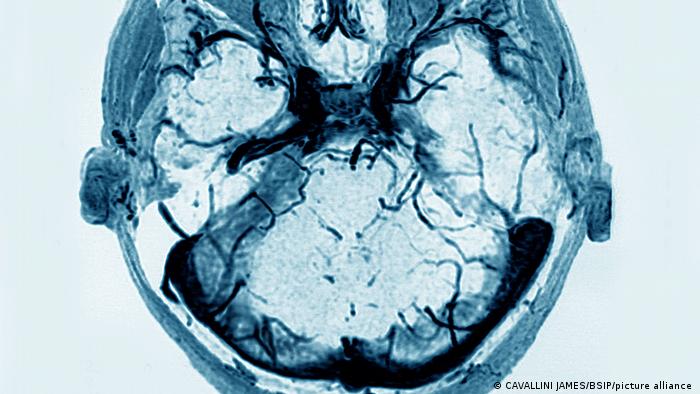

Tal y como recuerda, la trombosis venosa cerebral es un subtipo de ictus infrecuente en el que se ve comprometida la circulación en el sistema venoso del cerebro, dificultando el flujo de la sangre hasta el corazón y su oxigenación, llevando consigo la elevación de la presión intracraneal. "Según datos de la Sociedad Española de Neurología (SEN), la trombosis venosa cerebral representa menos del 0,5 por ciento de los casos totales de enfermedades cerebrovasculares que se producen en España y el riesgo de infarto se da solo en los casos extremos y con diagnóstico tardío", señala.

En cuanto al diagnóstico, el estudio de la trombosis venosa cerebral se realiza conjugando la historia clínica (sospecha clínica) y la exploración, junto a pruebas de neuroimagen como el TAC Craneal. "En el 30 por ciento de los casos, el TAC inicial es normal, por lo que se necesita completar con angio-TAC de senos venosos, así como resonancia magnética y angio-resonancia", precisa el especialista.